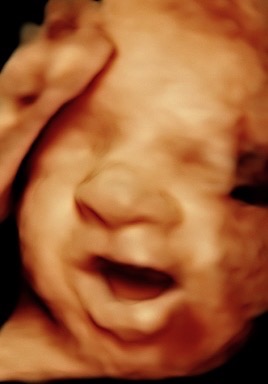

Hi, my name is Crystal Heller, and I’m the owner of Miracle 3D Moments. For the past five years, I’ve had the privilege of helping moms, dads, and families see and bond with their babies before they’re born. It’s been the most rewarding part of my life watching the smiles, the tears of joy, and the comfort that comes when a mom-to-be sees her little one moving, yawning, and even smiling.